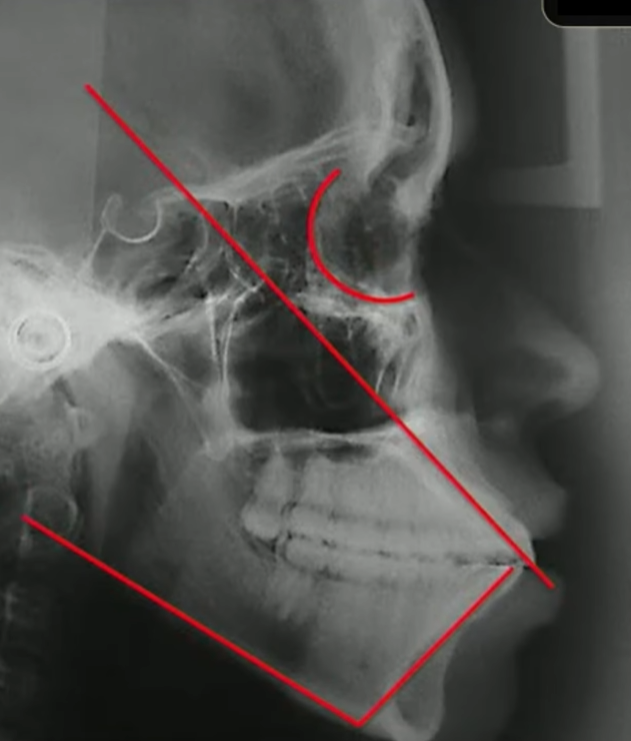

E eu também consigo traçar o meu incisivo inferior, medindo ele com a base mandibular:

Quando eu faço essa medida do incisivo inferior com a base mandibular, qual a minha intenção?

Eu quero saber também se esse incisivo inferior está mais ou menos com 90 graus em relação à base mandibular, nesse caso aqui eu tenho os incisivos bem vestibularizados.

Eu gostaria muito que tanto o superior quanto o inferior estivessem com uma inclinação dentro da normalidade

Para eu conseguir isso aqui nessa paciente dessa telerradiografia, obrigatoriamente eu tenho que fazer 4 extrações nessa paciente que eu mostrei para vocês.